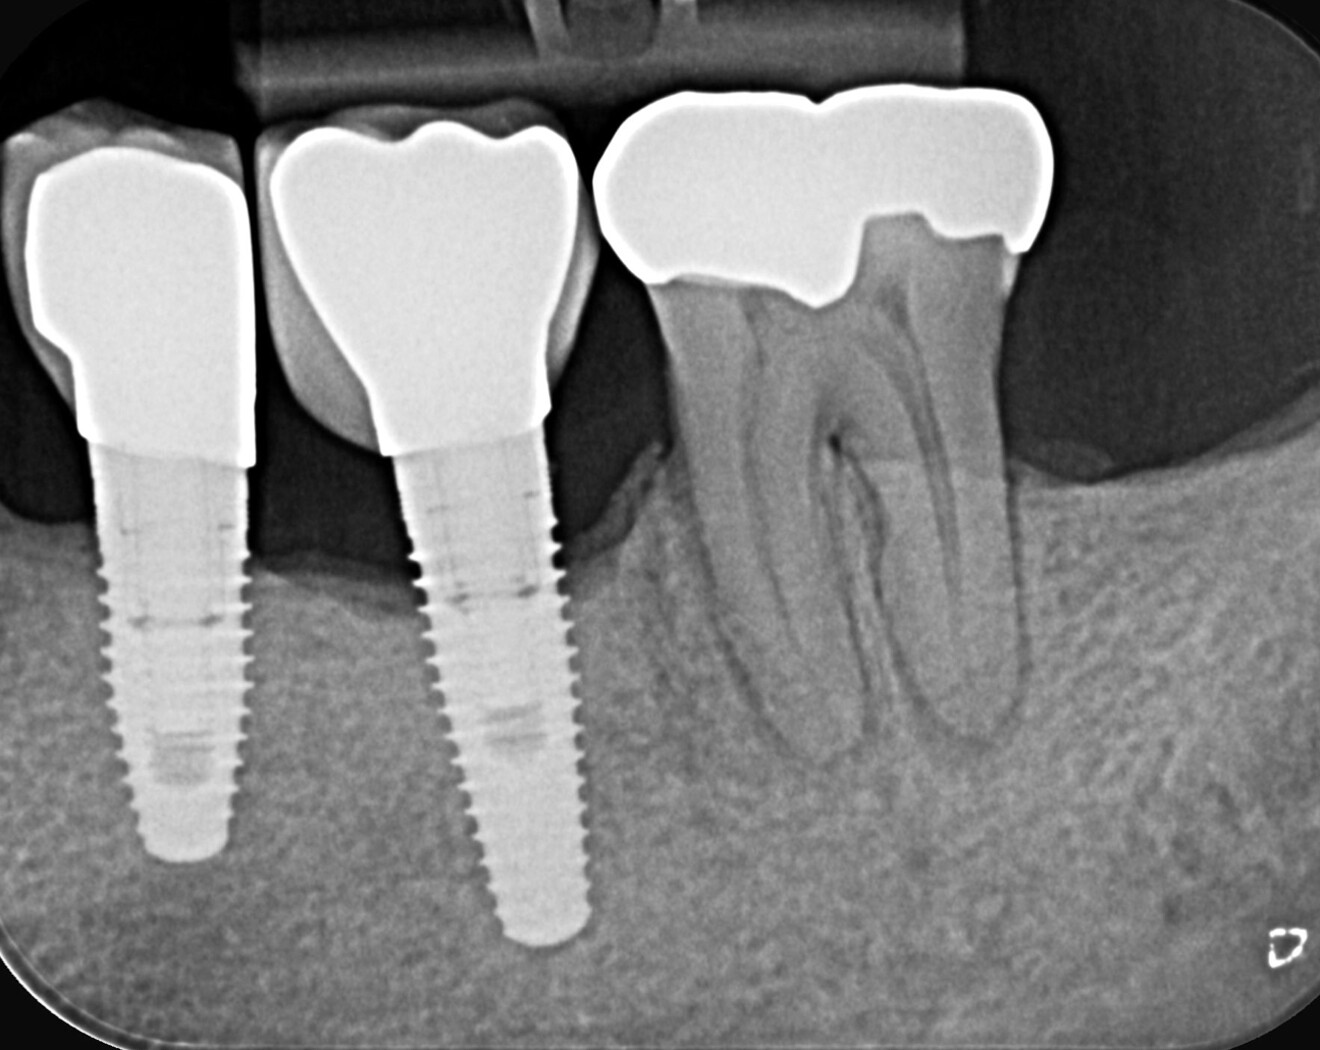

A patient with a periodontal issue was referred for the treatment of a maxillary and a mandibular molar. The maxillary molar was necrotic, and the preoperative radiograph showed a severely calcified pulp chamber and blocked root canal entrances (Fig. 7).

Fig. 7: Pre-op radiograph showing a maxillary first molar with a very calcified pulp chamber and narrow canals.

Fig. 8: Post-op radiograph of the root canal treatment done using Adaptive Motion with the narrow canal file sequence.